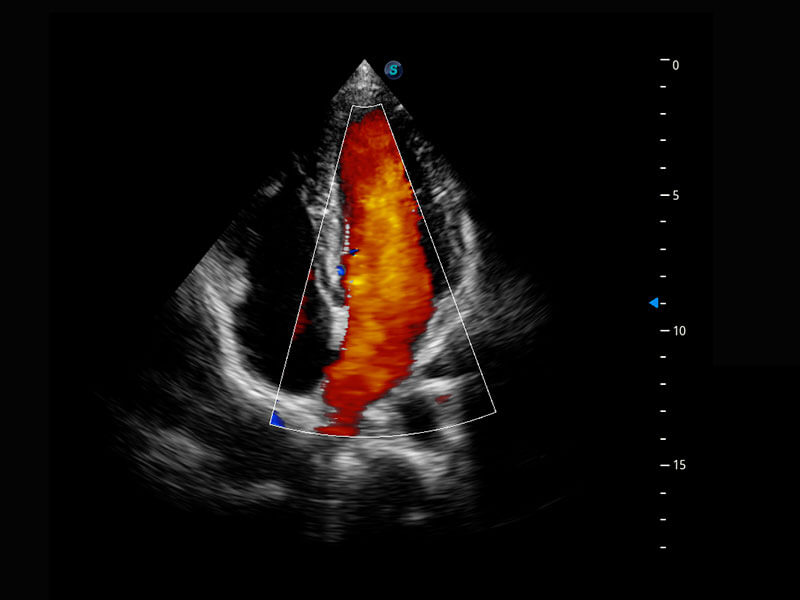

胎心筛查

P60搭载一系列胎儿心脏成像技术,实现精细的胎儿心脏评估。

• 四腔心血流